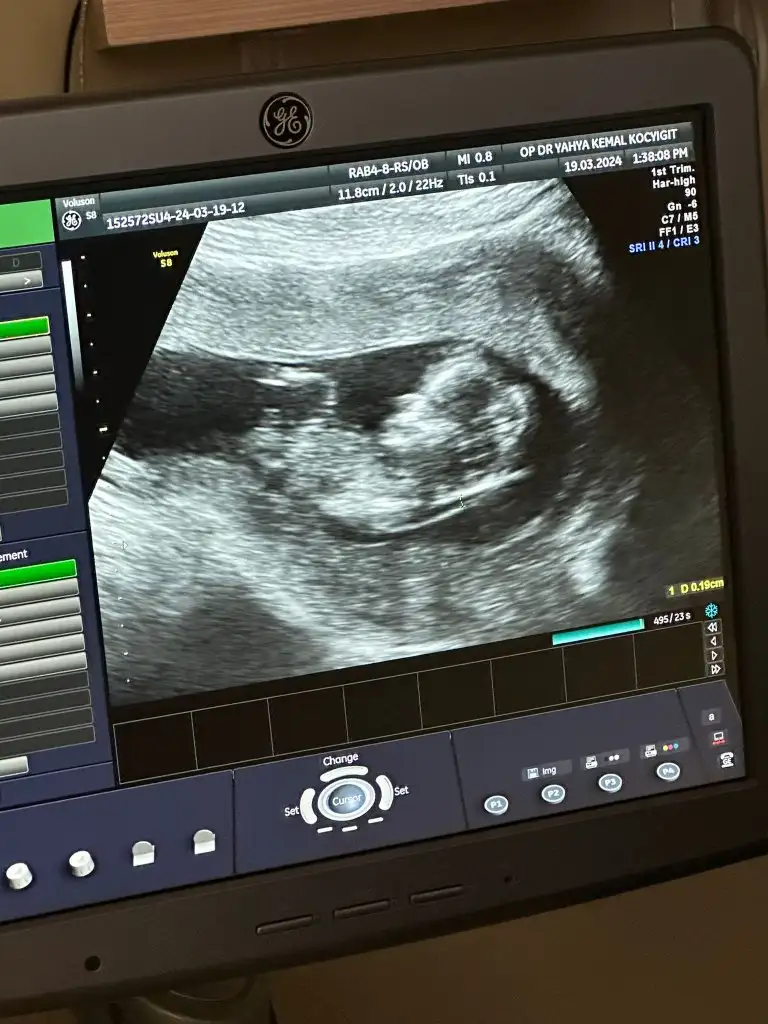

Cinsiyet tahmini yapabilen varmı

• 17134404001124555547007666287492.webp

17134404001124555547007666287492.webp

24,4 KB · Görüntüleme: 79